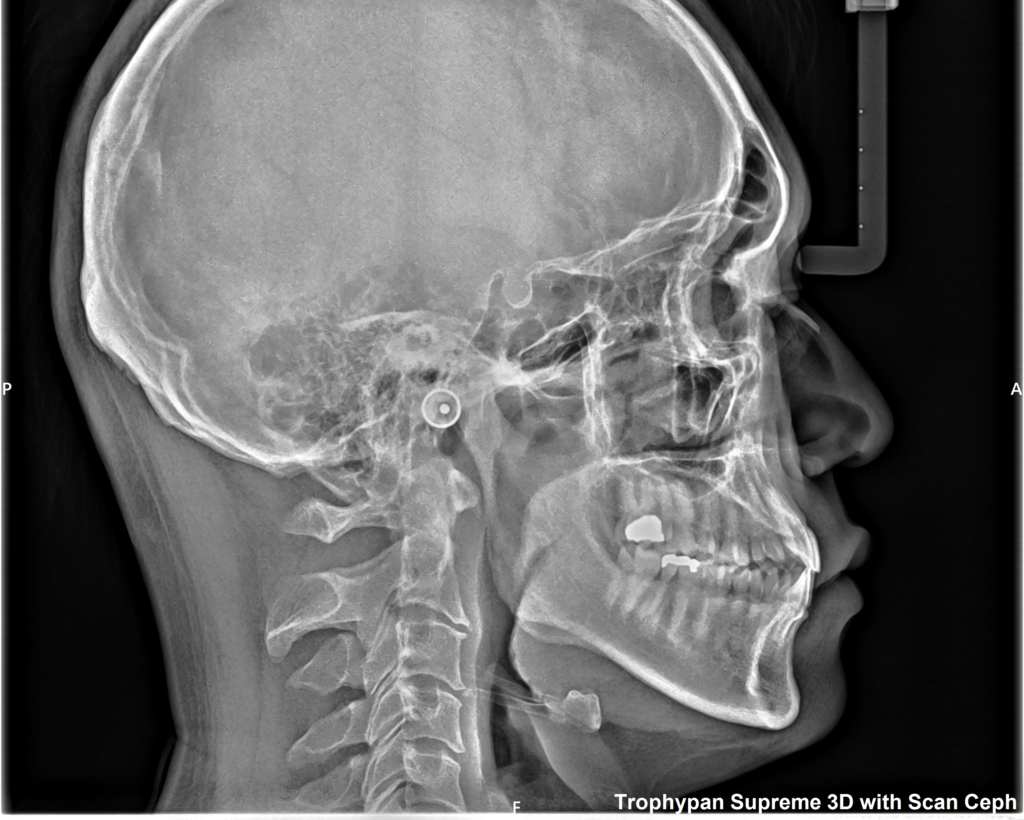

②セファロ写真

側貌写真では、頭部の位置に対する上下顎の前後関係(出っ歯や受け口など)や垂直関係(面長か丸顔かなど)を調べたり、歯の傾きや口元の突出度など様々な要因を数値化して正常値からどれくらい離れているかを確認します。

正貌写真では、正面から見た顔や顎の歪み、前歯の真ん中の位置などを確認します。